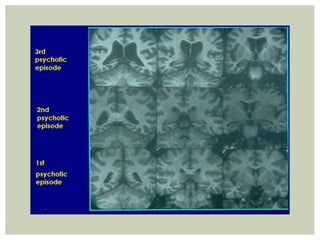

 De acuerdo a estudios de neuroimagen los

esquizofrénicos resistentes presentan atrofia cortical

con mayor frecuencia que los esquizofrénicos no

resistentes.

 En un estudio de 40 casos de pacientes

esquizofrénicos con RM 95 % de los resistentes

presentaban atrofia determinada por medición global

de volumen cerebral frente al 60 % de los no

resistentes